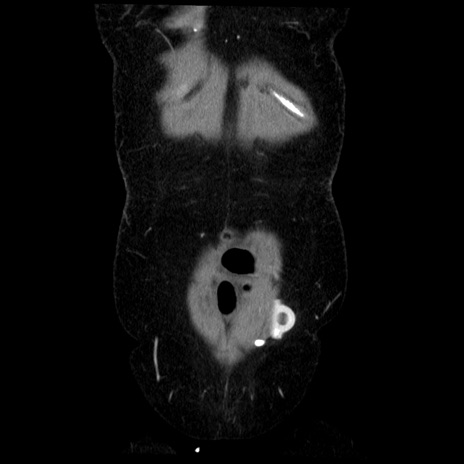

横断像